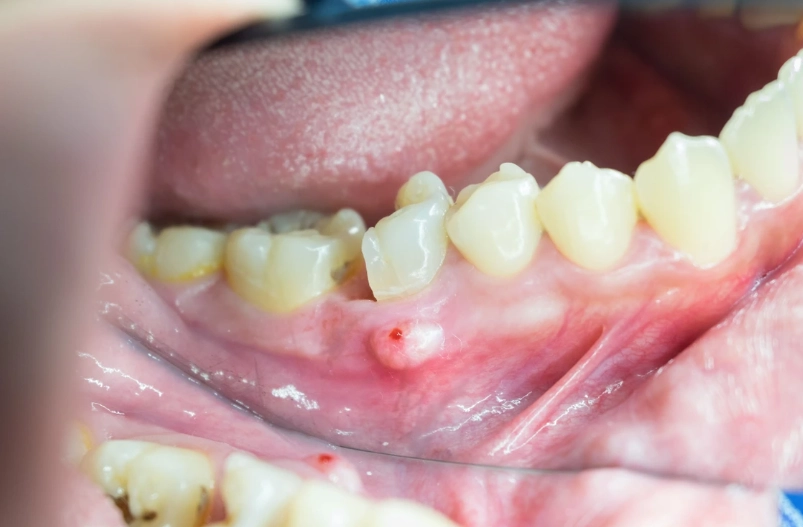

What a Periapical Abscess Really Is (And Why It's a Big Deal)

First things first, let's get clear on the enemy. A periapical abscess isn't a surface-level problem. It starts inside your tooth.

Think of your tooth like a tiny castle. The hard enamel is the outer wall. Inside is the pulp chamber—the castle's living quarters, full of nerves and blood vessels. The roots are the castle's foundations, buried in your jawbone. If bacteria breach the walls (through a deep cavity, a crack, or an old filling), they invade the pulp. The immune system fights back, and that battle creates pus. That pus has nowhere to go, so it builds up at the very tip (apex) of the root, in the bone. That's your abscess.

And it's not just sitting there. It's actively destroying bone. It's looking for an escape route, which can lead to swelling in your gums or face. Left unchecked, it can become a serious health risk. So diagnosing its exact size, shape, and path is critical.